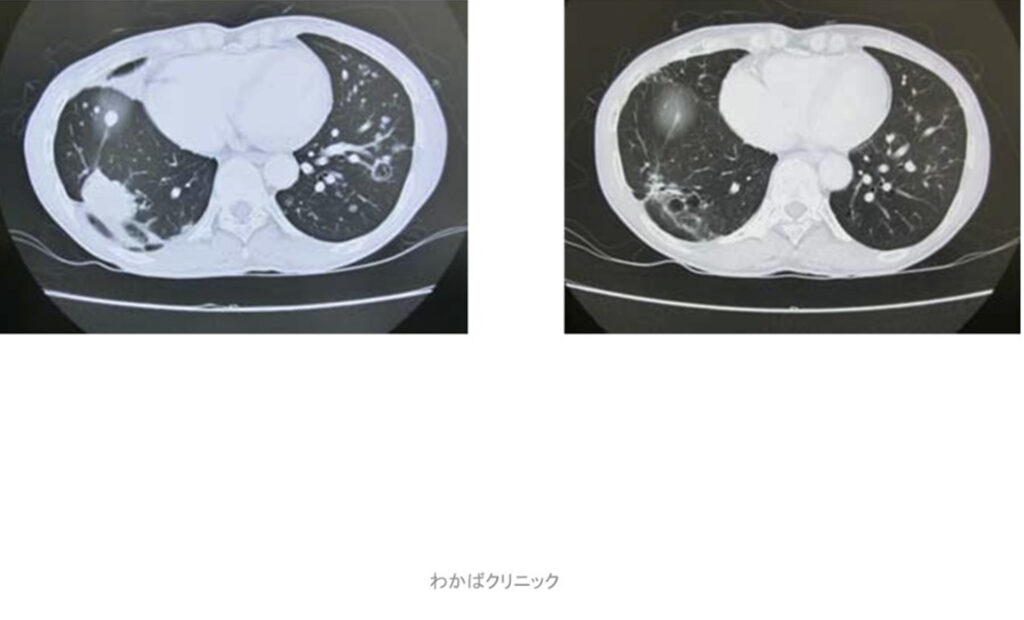

- 西洋医学的な効果判定(必ず必要です)

- CT・MRI・超音波検査 他